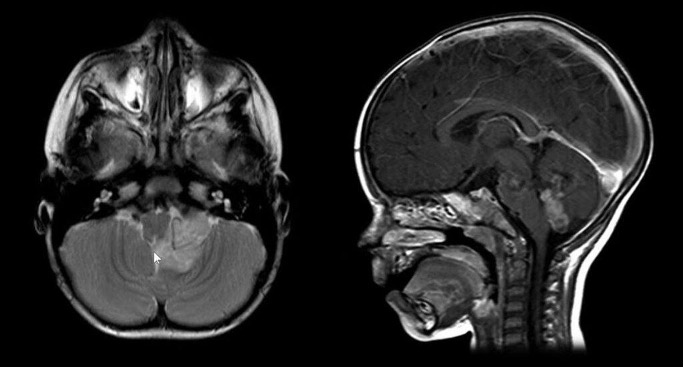

El estudio inicial para el diagnóstico de estos tumores es la resonancia magnética cerebral con gadolinio o medio de contraste. En este estudio, normalmente se identifica un tumor en el interior del cuarto ventrículo, que se origina en su piso. Por su parte, los tumores que se encuentran en el interior de la médula espinal suelen ser extensos a nivel del canal medular.